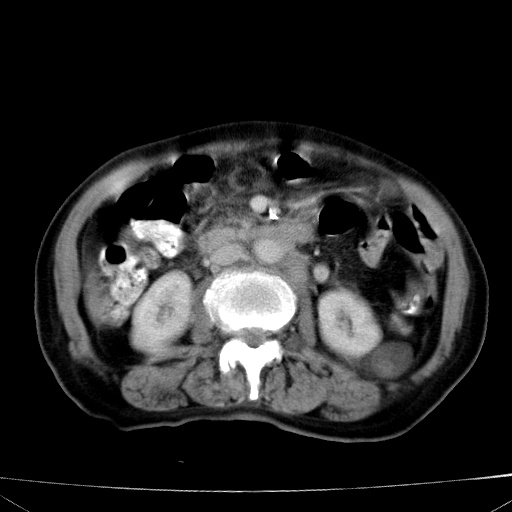

网站人气太旺!昨天的帖子就沉到海底,只好再发贴!ct18338:女 78岁,肝胆病变,已增强,再会诊!原帖链接:http://www.radida.com/bbs/forum.php?mod=viewthread&tid=50032

1)考虑胆囊癌侵犯肝脏并肝门区、腹膜后及右侧膈角后淋巴结转移。2)肝左叶近肝顶部囊肿。3)肝左叶肝内胆管结石。4)左肾近下极囊肿。